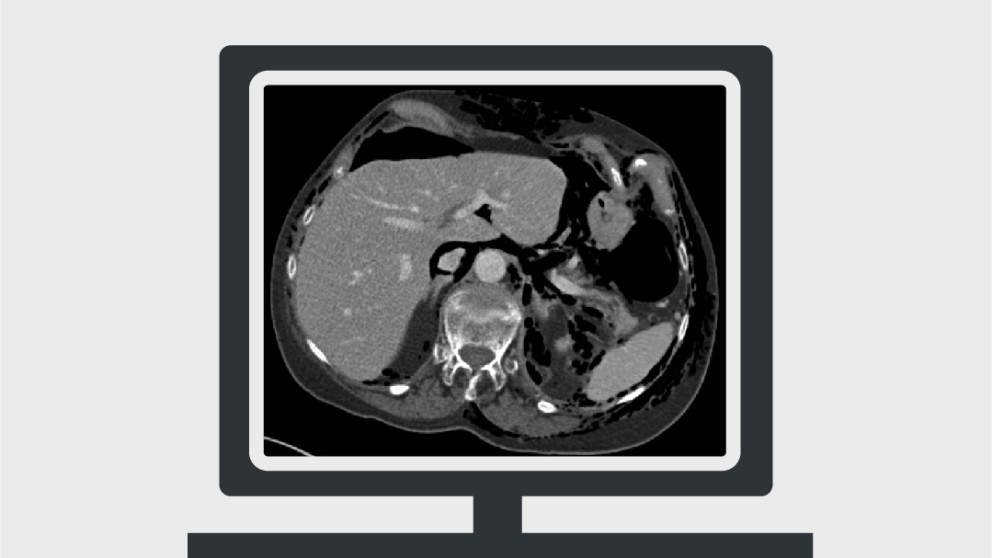

Abdominal CT (computed tomography) is among the most common imaging tests performed for the investigation of acute abdominal pathology. There are many pitfalls that clinicians and radiologists should be aware of when requesting these studies and interpreting the findings. This article covers ten mistakes frequently made with abdominal CT, focusing on gastrointestinal tract and hepatobiliary pathology. These mistakes and their discussions are based on the available literature where possible and thereafter on our clinical experience.

Mistakes in acute abdominal CT and how to avoid them

Hameed Rafiee, Stuart Taylor

Rafiee H and Taylor S. Mistakes in acute abdominal CT and how to avoid them. UEG Education 2017; 17: 18–23.